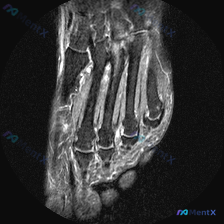

足部MRI提示软骨异常?其实核心问题藏在这个关节里

看到一个足部MRI读片病例,初始问题是观察影像上的软骨异常,整理了完整的影像特征和分析思路分享给大家。

这是足部MRI冠状位影像,大概率为T2压脂序列,骨髓和软组织水肿呈明显高信号,这点对诊断非常关键。

- 骨骼:病变累及中足跖骨区域,第2、3、4跖骨基底可见广泛骨髓异常高信号(水肿表现),骨皮质连续性尚可,未见明确骨折错位线

- 关节:Lisfranc(跗跖)关节复合体区域明显异常,关节间隙周围软组织肿胀、信号增高

- 软组织韧带:跖骨间隙可见弥漫性高信号(软组织水肿),足背、足底侧软组织均有弥漫性肿胀,信号不均匀增高

病灶以Lisfranc关节区为中心,呈片状弥漫分布,边界模糊,未见明确占位性肿块或囊性变边界。